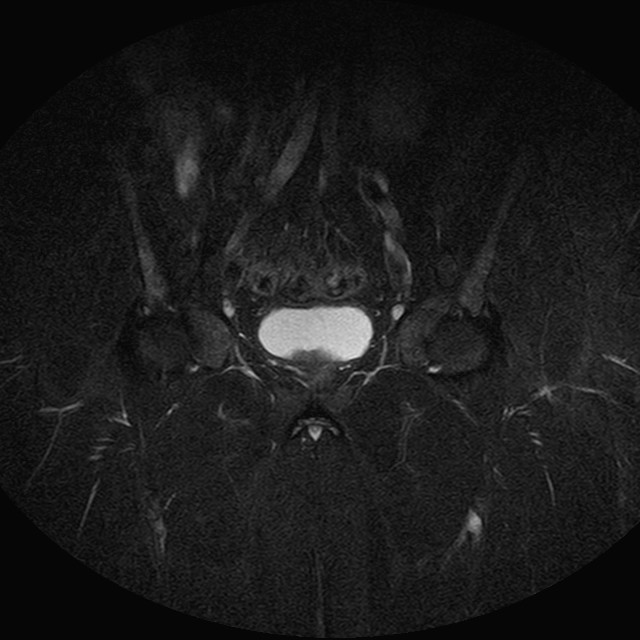

Esami: RMN BACINO

eSTIR

Evidenti e simmetriche alterazioni osteofitosiche in regione coxo femorale con riduzione delle rime articolari. Degenerazione completa del cercine glenoideo. Non attuali segni di versamento articolare. Non segni di edema osseo che escludono attuale algodistrofia od osteonecrosi. Lieve e simmetrica riduzione del trofismo della muscolatura glutea.